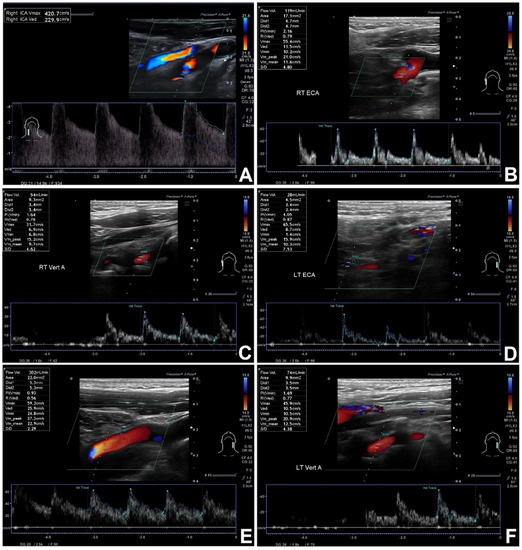

Figure 2.

CBF estimation in symptomatic 67 years old patients with significant RICA stenosis and no volumetric flow compensation in other extracranial arteries. (A)—RICA—significant >95% stenosis, flow volume distally 43 mL/min. (B)—RECA with flow volume of 119 mL/min, (C)—RVA with flow volume of 54 mL/min, (D)—LECA with flow volume of 28 mL/min, (E)—LICA with flow volume of 302 mL/min, (F)—LVA with flow volume of 74 mL/min. CBF of 620 mL/min—no compensation.